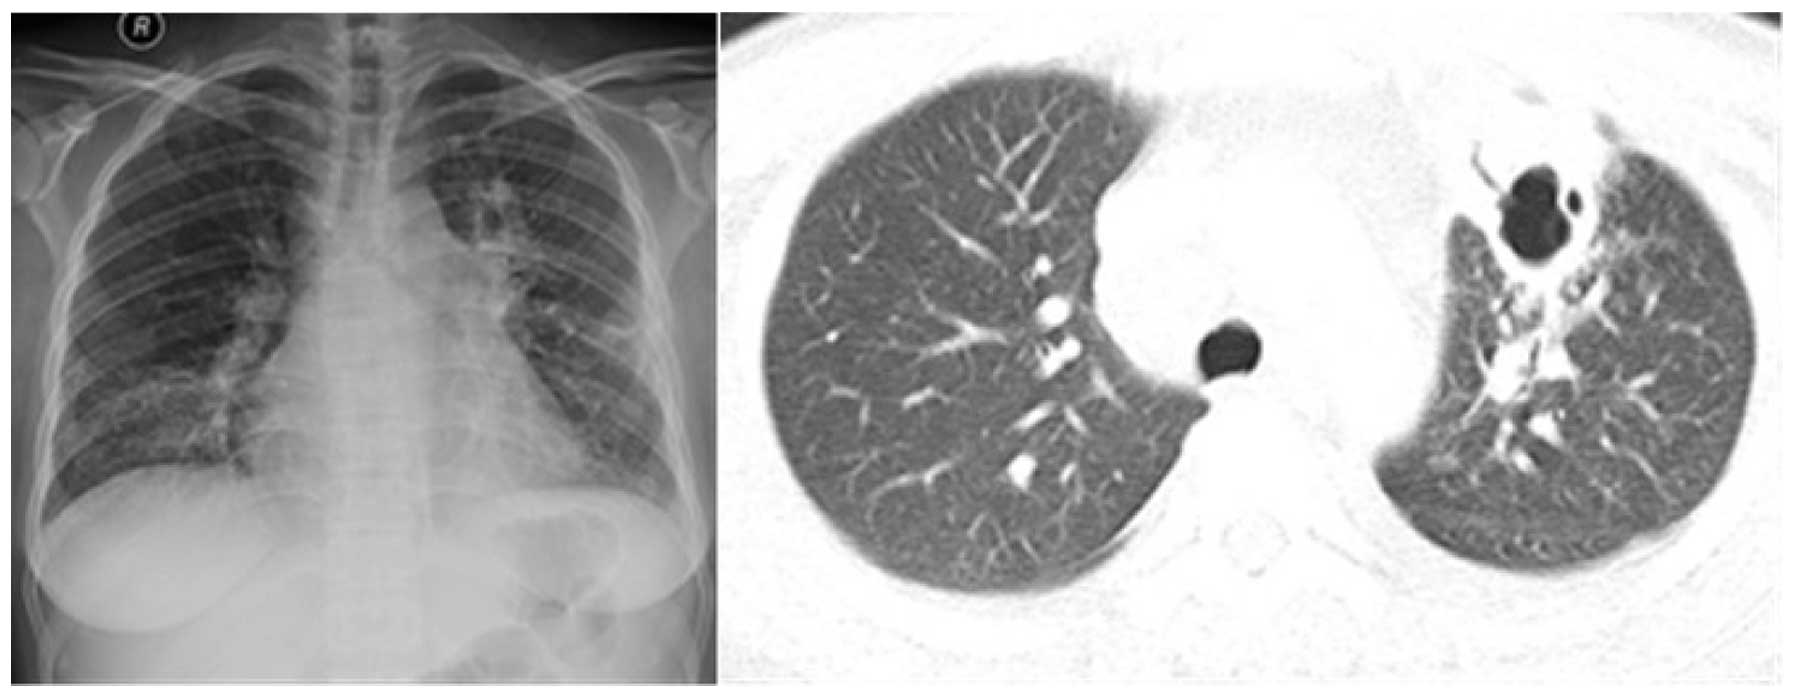

The CT and enhanced MR show multiple bone destruction and masses in skull, with ring-enhanced abscesses in scalp (Fig. 2), and bilateral neck, bilateral upper arm, head and face have multiple visible purulent mass. A culture of blood and cyst fluid revealed P. marneffei infection (Fig. 3). The patient was administered 2 weeks of antifungal therapy, and the patient's condition was markedly improved. The exudative lesions significantly improved absorption and systemic multiple pustule subsided. Patients and families must consider the costs of treatment. It was recommended that the patient return to the local hospital for follow-up treatment following discharge from The Second Xiangya Hospital of Central South University on March 10th 2015. Following discharge, liposomal amphotericin B was used (initial dose, 25 mg/day for 4 days, increasing to 150 mg/day for 12 days, then the total applications of amphotericin B liposome was up to 2,000 mg). After three months of treatment, the abscesses of the head, face and other body parts disappeared and the enlarged lymph nodes disappeared. The sizes and number of lesions in the chest and abdomen were significantly reduced. The symptoms of the patient were significantly improved, so she decided to stop antifungal treatment without medical advice. At 10 months after stopping treatment, the abscesses in the head and neck, the left breast, and right leg reappeared. After the anti-tuberculosis treatment at the local hospital, the condition gradually deteriorated, and pleural and pericardial effusion was observed. The patient was re-admitted to The Second Xiangya Hospital of Central South University again. A culture of the systemic lesion abscess pus once again confirmed P. marneffei infection. After a period of antifungal therapy with amphotericin B (daily 0.6 mg/kg) for 2 weeks of treatment, followed by oral itraconazole (400 mg/day) maintenance therapy, disappearance of the abscesses were confirmed, body temperature returned to normal, and pleural and pericardial effusion disappeared. To date, recurrent disease has not been detected.

Figure 2.

The computed tomography and enhanced magnetic resonance imaging revealed multiple sites of bone destruction an masses in the skull, with ring-enhanced abscesses in the scalp.